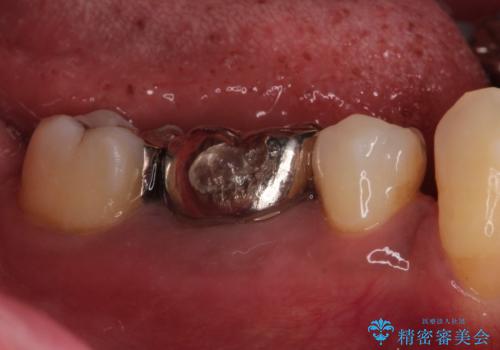

- 奥歯が痛いことを主訴に来院されました。

遠心根に歯根破折を認め、保存不可と判断しブリッジにて欠損補綴を行なっております。